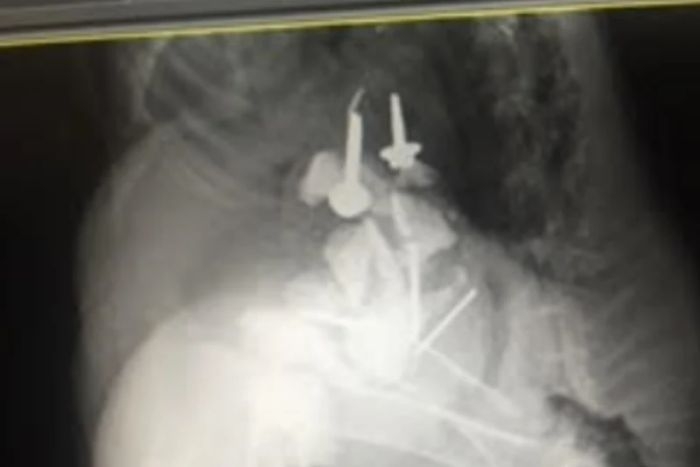

• 布里斯班鸸鹋肚中取出大量钉子螺丝和石头!竟还悠闲城中一日游!

我们听说过考拉和袋鼠跑进商场一日游的情况,常常会惹得人们竞相拍照晒图! 但是下面这位却是个“稀客”,而且这位稀客的城中一日游还差点让自己有了生命危险! 本周三,布里斯班街头迎来了一位漫无目的的游荡 ...